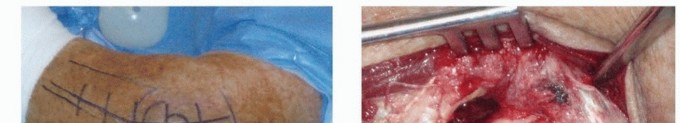

Patient positioning must be carefully selected based on the anticipated surgical approaches and the potential need for intraoperative fluoroscopy. Most commonly, the patient is positioned supine on the operating table under general anesthesia, with the operative limb supported on a radiolucent hand table. A sterile tourniquet is applied to the proximal arm to provide a bloodless field. This position provides excellent access for a lateral approach and allows for easy extension to a medial approach if necessary. The arm can be freely manipulated to assess stability under fluoroscopy.

The lateral approach is the workhorse for the treatment of terrible triad injuries, providing access to the LCL complex, the radial head, and, in many cases, the coronoid. A direct lateral incision is made, typically utilizing the Kocher interval between the anconeus and the extensor carpi ulnaris (ECU). However, the astute surgeon will often abandon formal anatomic intervals and instead utilize the traumatic dissection that occurred at the time of injury. In most cases, the LCL and common extensor origin have been avulsed from the lateral epicondyle, creating a massive traumatic window directly into the joint. If an anteromedial facet fracture is present, a separate medial incision is utilized. The medial approach involves identifying and protecting the ulnar nerve, followed by splitting the flexor carpi ulnaris (FCU) or utilizing an "over-the-top" approach anterior to the medial epicondyle to gain orthogonal access to the coronoid.